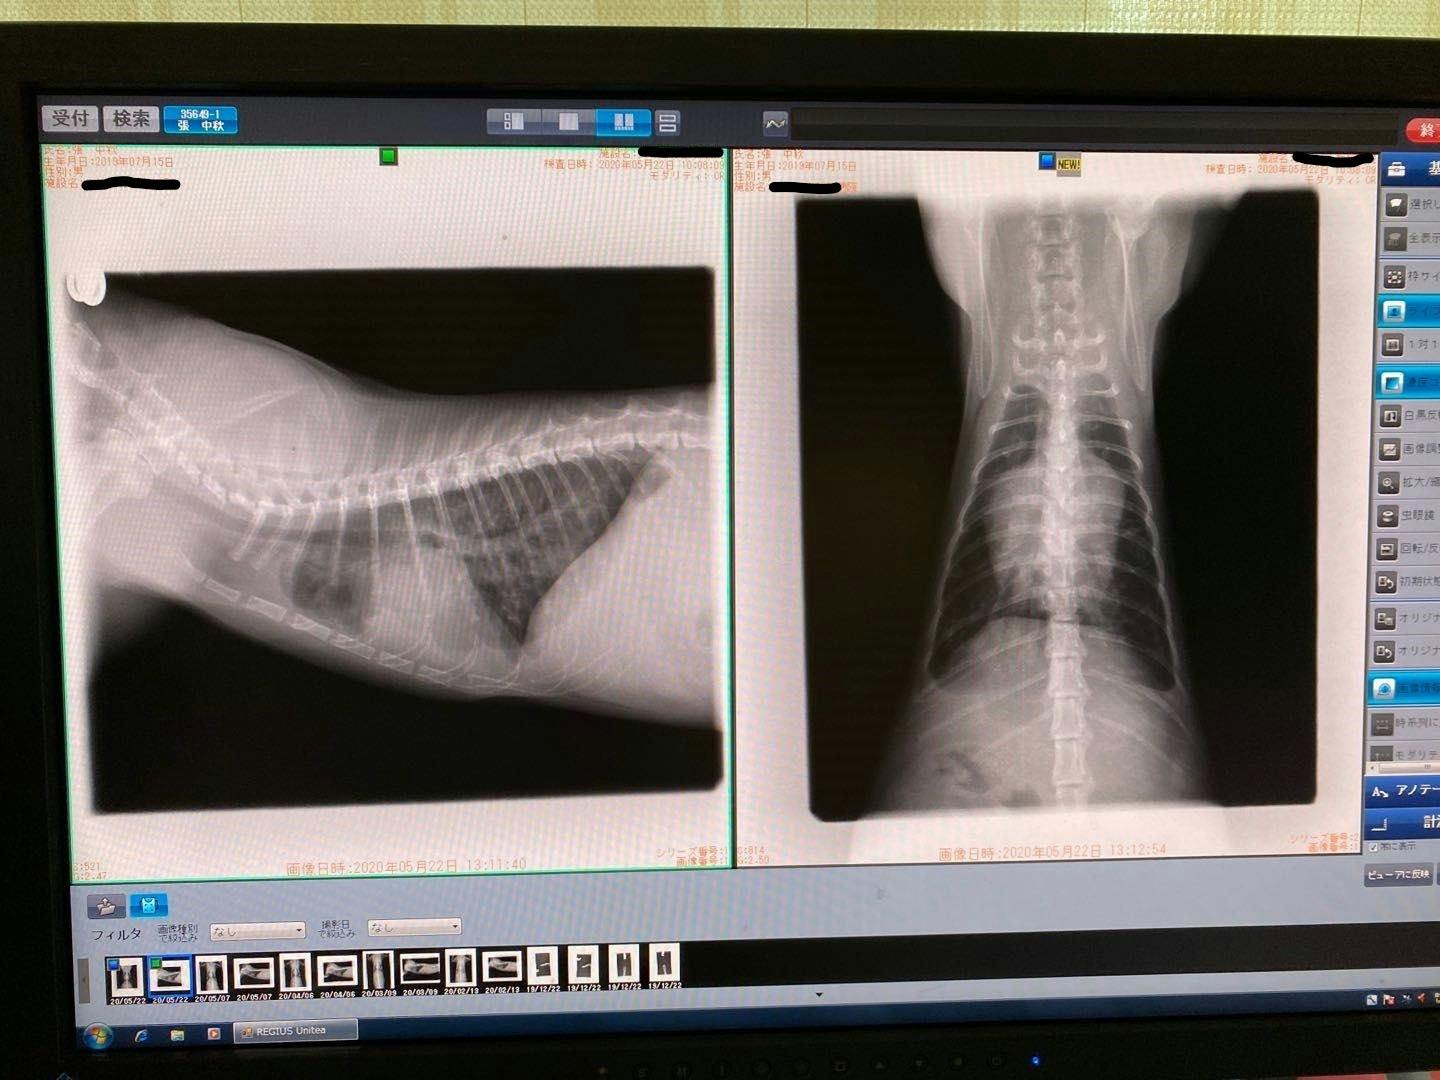

中秋ちゃんが今月の22日に猫伝染性腹膜炎(以下FIP)に発症しました。胸と腹は水が溜まって、肝臓が肉芽腫があります。この病気は発症すると、個体差によって数日から数か月しか生きれません。その日から中秋ちゃんが元気なく何も食べずになりました。23日いつもお世話になる動物病院に言って、FIPが発症と言われました。病院の方はステロイドと痛み止めを使ってできるだけ楽してしかできません。安楽死も方法の一つと言われた。

2/13去勢手術するため、身体検査をするとき、肺の中に薄い水影があって、念のため詳しい検査を行いました。

症状が軽い、判断が難しく、少し観察の時間が必要けど、最悪の場合はFIPを罹っているの可能性があると言われて、でも別の病気の可能性もあると言われました。3/9でレントゲン検査すると、水影が少し薄くになって、4月の検査も同じになって、FIPの可能性ではないかもと思います。けど、5月の検査はあまり変わらないになって、22日で急に発症になりました。前を振り返って見て、ずっと自分を責め続いている。

5/25家の近くの協力病院に行って、痛く辛い検査をして、中期混合型と診断されました。

腹水がたまっています

肉芽腫が見つかります

39℃の熱と重度の貧血もあります

強い炎症もあります